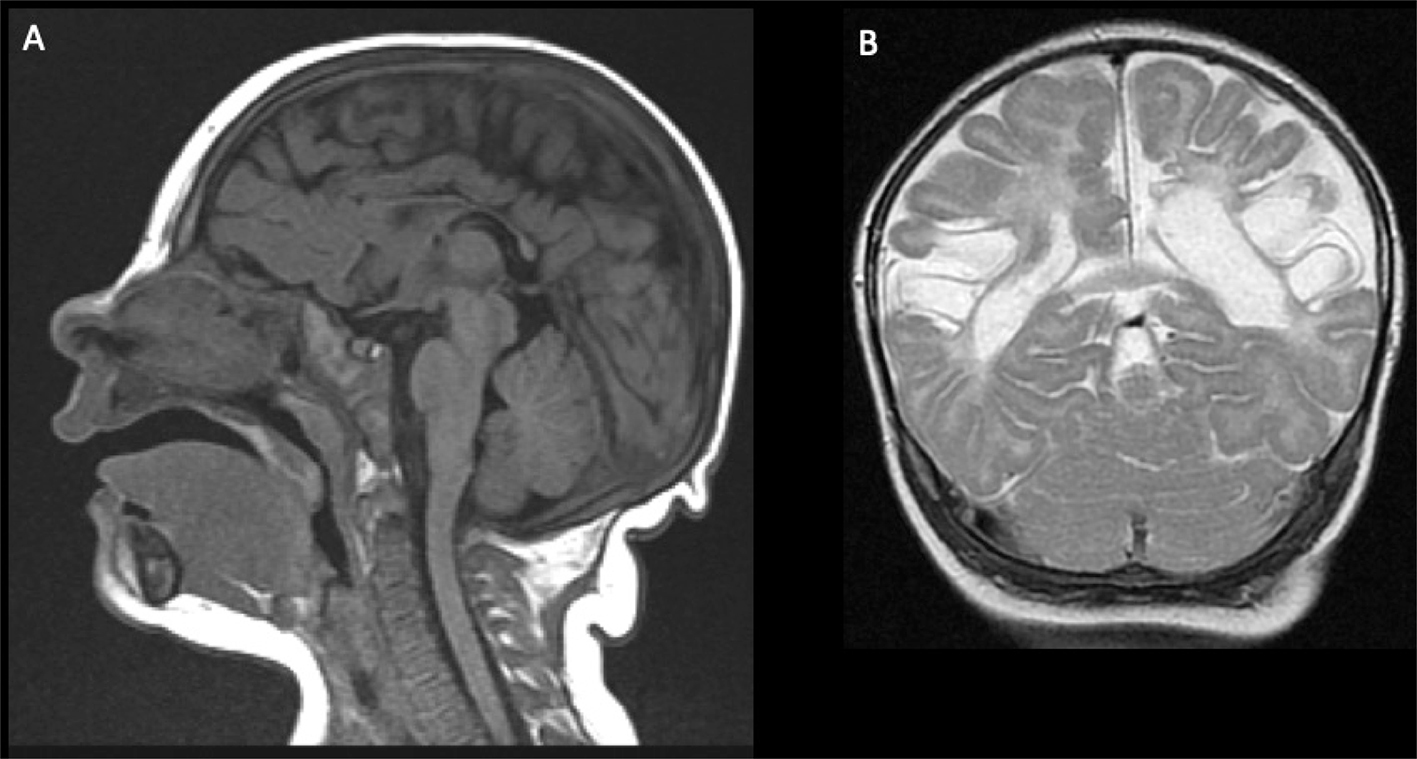

Venous infarct/CSVT

Fig 9